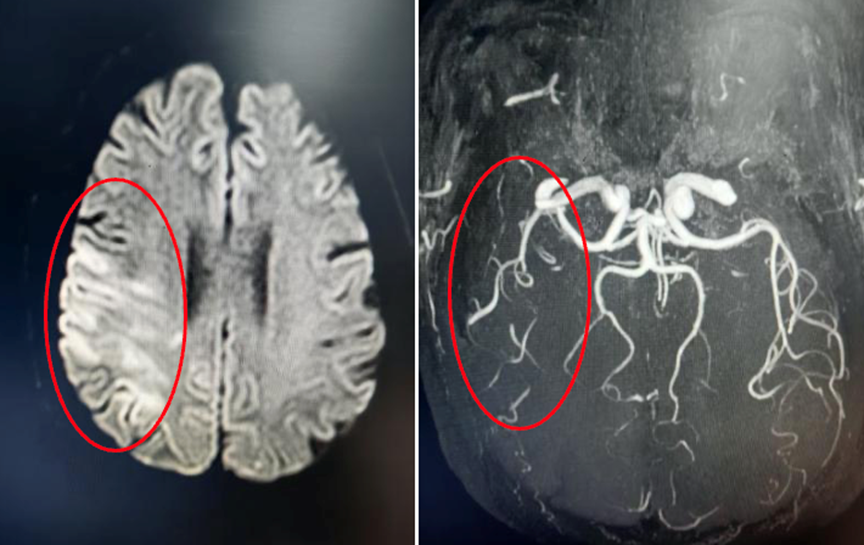

据悉,按照得分高低,贵州省人民医院口腔科5个案例均入百强,其中3例进入全国前十。贾莹主任医师《一例脑瘫患儿开合的早期矫治》荣获第7名、《正畸主导多学科治疗儿重牙外伤及颌骨骨折》荣获第10名;何欢住院医师《重度慢性炎变含牙囊肿-囊内多颗埋伏“异位”牙早期助萌矫治》荣获第8名;徐秋艳副主任医师《乳牙全牙列反合的早期矫治》荣获第56名;陈泽策住院医师《牙再植与早期矫治联合治疗》荣获第85名。